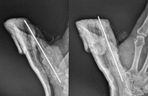

• Operacja trwała ponad 2,5 godziny – palec udało się przyszyć i przywrócić krążenie.

Transport karetką z Wielkopolski do Białegostoku trwał kilka godzin. Operacja rozpoczęła się tuż po północy i trwała ponad 2,5 godziny. Lekarze walczyli o każdy milimetr naczyń i nerwów. Udało się – palec został przyszyty i jest ukrwiony. – To był czas graniczny, ale dzięki determinacji pacjenta i zespołu wszystko się powiodło – podkreśla dr Komarnicki.